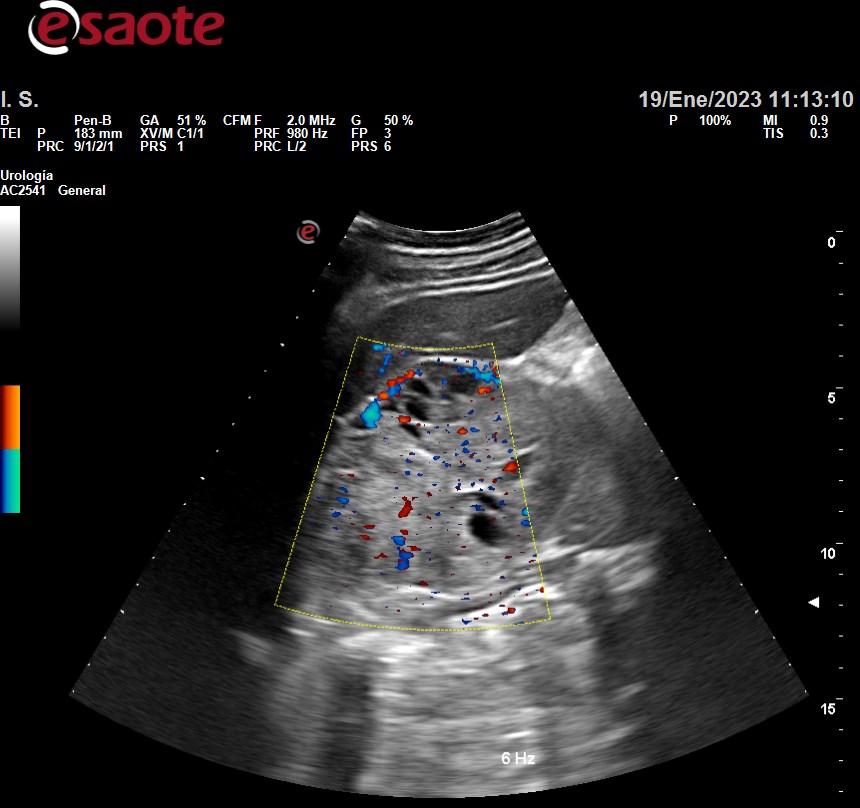

Hallazgos ecográficos

Siguiente hallazgo:

• Riñón derecho aumento tamaño 12.2 x 76.5 x 64.2, irregular, heteroecoico con presencia de áreas hipoecoicas sin litiasis ni dilatación sistema pielocalicial.

Ecografía hospital: tumoración renal derecha primaria, predominantemente sólida con zonas quísticas, en cortical externa interpolar - polar inferior, con proyección al seno renal, sin infiltración del pedículo vascular.